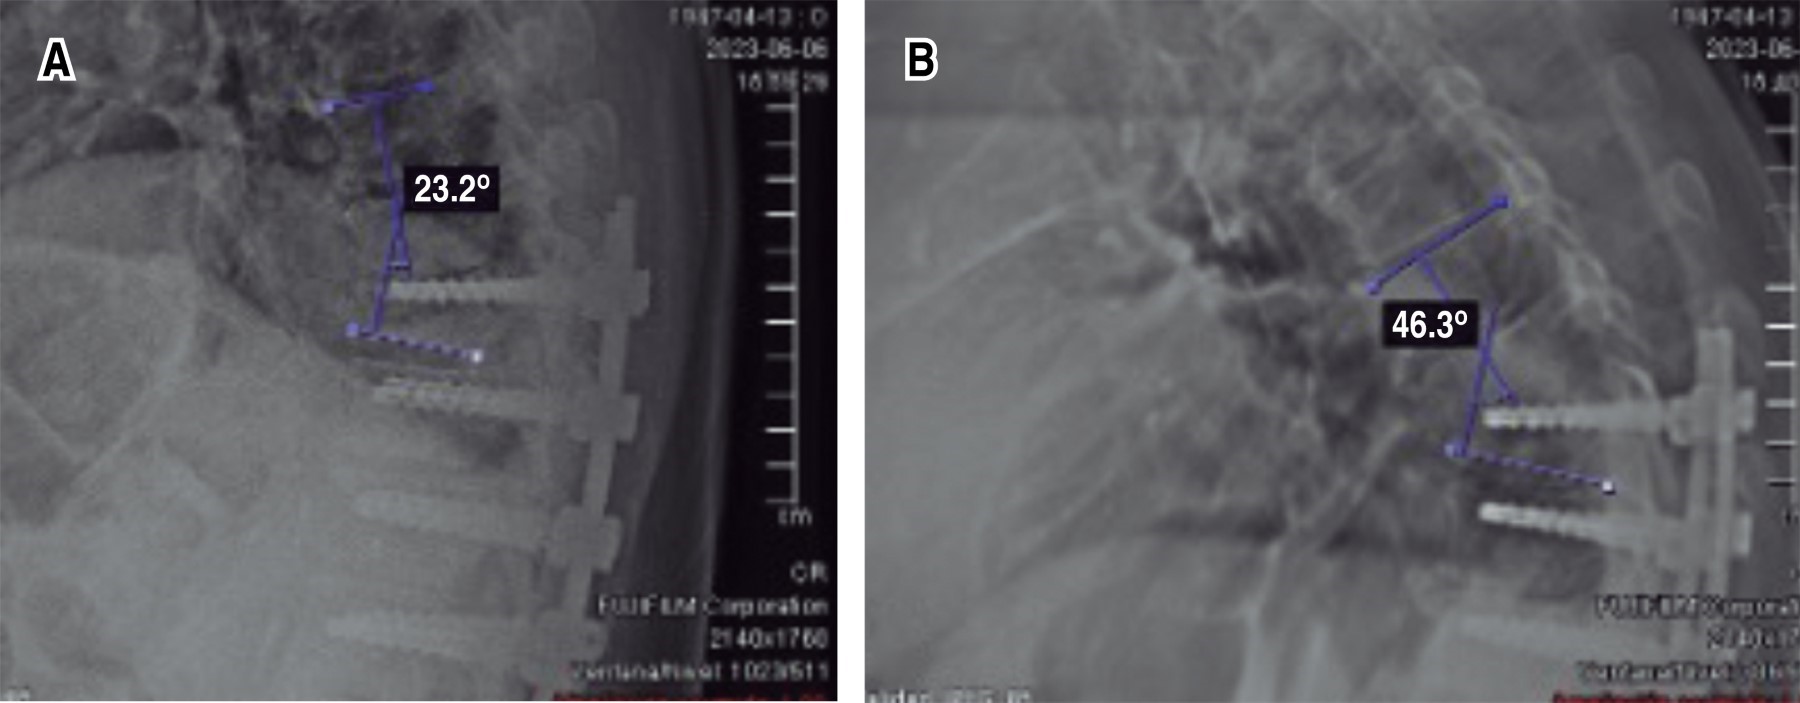

Paciente masculino con escoliosis lumbar degenerativa acompañado de enfermedad de Parkinson (EP). Se instrumenta únicamente los niveles necesarios para corrección de la deformidad coronal, como descompresión de los niveles con estenosis. A pesar de un control radiológico inmediato satisfactorio, en los días posteriores el paciente se aqueja de dolor a nivel de la columna torácica. Rayos X de seguimiento evidencian fractura de la vértebra más cefálica instrumentada. Debido a múltiples comorbilidades, se decide manejo conservador, esperando consolidación del segmento lesionado. Sin embargo, a pesar del tratamiento médico, es llevado cinco meses postoperatorio a sala de operaciones para prolongación de la instrumentación, realizando una transición de una fijación rígida a una semirrígida. El objetivo de la publicación es poner en contexto acerca de la dificultad que conlleva el manejo de un paciente que padezca EP combinado con algún padecimiento degenerativo de la columna.REFERENCIAS (EN ESTE ARTÍCULO)